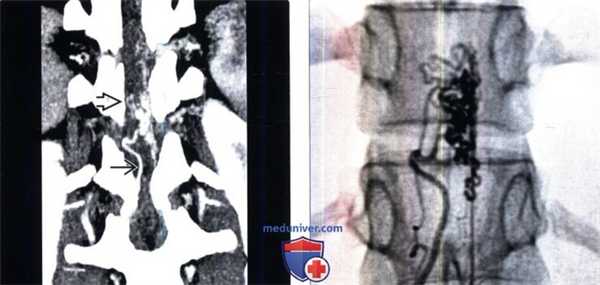

(Справа) Фронтальная КТ-ангиография: фистула 1 типа, расположенная на уровне грудного отдела позвоночника в области правого неврального отверстия и сопровождающаяся расширением дренирующих вен ниже фистулы.г) Патология:

(Слева) Сагиттальный срез, STIR МР-И: гиперинтенсивность сигнала на всем протяжении спинного мозга и нечетко ограниченные сосудистые полости вдоль вентральной его поверхности. Также виден ограниченный участок низкого сигнала, который при проведении ангиографии оказался высокопоточной аневризмой.

(Справа) На ангиограмме в прямой проекции (артериальная фаза) контрастирован крупный сегментарный питающий сосуд спинного мозга, кровь из которого напрямую, без промежуточного узла, шунтируется во фронтальное венозное сплетение. В области фистулы образовалась высокопоточная аневризма.в) Дифференциальная диагностика сосудистой мальформации 4 типа:

(Слева) На сагиттальном Т1 -ВИ у пациента с интрадуральной фистулой 4 типа визуализируются многочисленные извитые сосудистые полости вдоль дорзальной поверхности спинного мозга.

(Справа) Ангиография в прямой проекции: фистула 4 типа, кровоснабжаемая правой корешковой артерией, контрастированы многочисленные расширенные перимедуллярные вены.2. Стадирование, степени и классификация сосудистой мальформации 4 типа:

(Слева) На фронтальной КТ-ангиограмме визуализируется крупный клубок сосудов вдоль вентральной поверхности спинного мозга, кровоснабжаемый правой корешковой артерией и характеризующийся расширением вен на поверхности спинного мозга.

(Справа) Ангиография в прямой проекции: сосудистая мальформация, кровоснабжаемая корешковой артерией на поверхности спинного мозга. Шунтирование крови осуществляется на уровне спинного мозга (4 тип), а не на уровне твердой мозговой оболочки (1 тип).г) Клинические особенности: